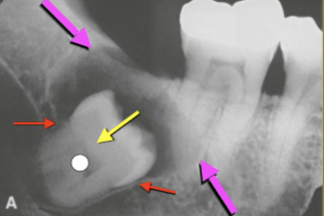

Describe this Radicular Cyst

Epicenter at apex (usually evidence of dental disease or trauma)

Well-defined, corticated

Lucent

Circular

Resorption, Displacement, Expansion (effect on adjacent structures)

Why is this Radicular cyst less circular/oval in this case?

What is the Green Dot?

Submandibular Fossa

What is the Purple Dot?

Radicular Cyst